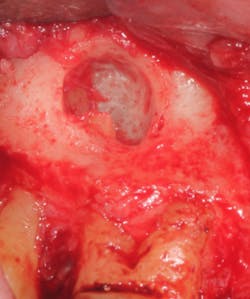

A split- to full-thickness intrasulcular incision was made on the facial of teeth Nos. 2 through 4. Upon completion of flap elevation, an intraosseous cyst associated with the distobuccal root of No. 3 was noted perforating the buccal plate and adherent to the overlying flap (figure 2). A sharp dissection separated the cyst from the flap (figure 3), and the cyst—measuring roughly 1.0 x 0.75 x 0.5 cm—was enucleated intact, leaving an intraosseous defect (figures 4a and 4b).